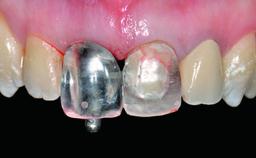

Replacement of an Upper Right Central Incisor with Root Resorption: Ridge Preservation, Delayed Placement of an NC Bone Level Roxolid Implant

Loading Protocol Conventional or early

Retention Screw-retained Screw-retained

Provisional Implant-Supported Prosthesis Prosthodontic margin > 3 mm apical to mucosal margin Prosthodontic margin > 3 mm apical to mucosal margin

Interim Prosthesis during Healing Fixed Fixed